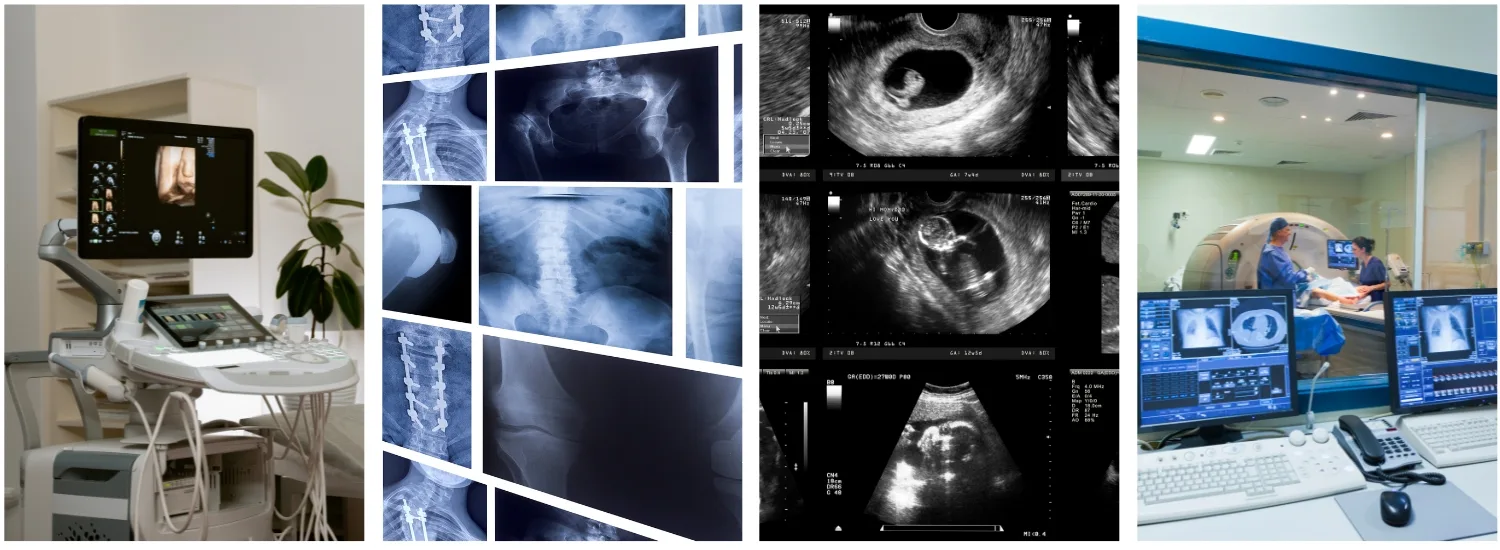

At Gopi Krishna Hospital, Mathura, we pride ourselves on offering one of the most advanced and ethical Radiology Departments in the region. With a commitment to accuracy, safety, and patient-centered care, our Radiology Department comprises two major units:

• X-Ray Unit

• Ultrasound Unit

Types of Ultrasound Services Offered

We provide a comprehensive suite of ultrasound services, including:

• Transabdominal Scan – Detailed imaging of the whole abdomen

• Transvaginal Scan (TVS) – Specialized imaging for uterus and adnexa

• 3D Ultrasound – Enhanced visualization for obstetric and gynecologic evaluations

• 4D Ultrasound – Real-time fetal imaging with motion

• Color Doppler Studies – Vascular flow and circulation assessment

• Anomaly Scans – Early detection of fetal abnormalities

• NTNB (Nuchal Translucency & Nasal Bone) – Essential scan for early chromosomal screening

• Fetal Growth Monitoring – Regular tracking of fetal development

• Follicular Monitoring – Ovulation tracking in fertility treatment

• Sono Salpingography (SSG) – Evaluation of fallopian tube patency

Each scan is conducted with utmost care, privacy, and precision by our trained sonologists under the supervision of Dr. Neerja Goyal.